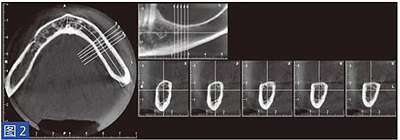

圖2:病例1. 術(shù)前左下頜骨CBCT 掃描結(jié)果。